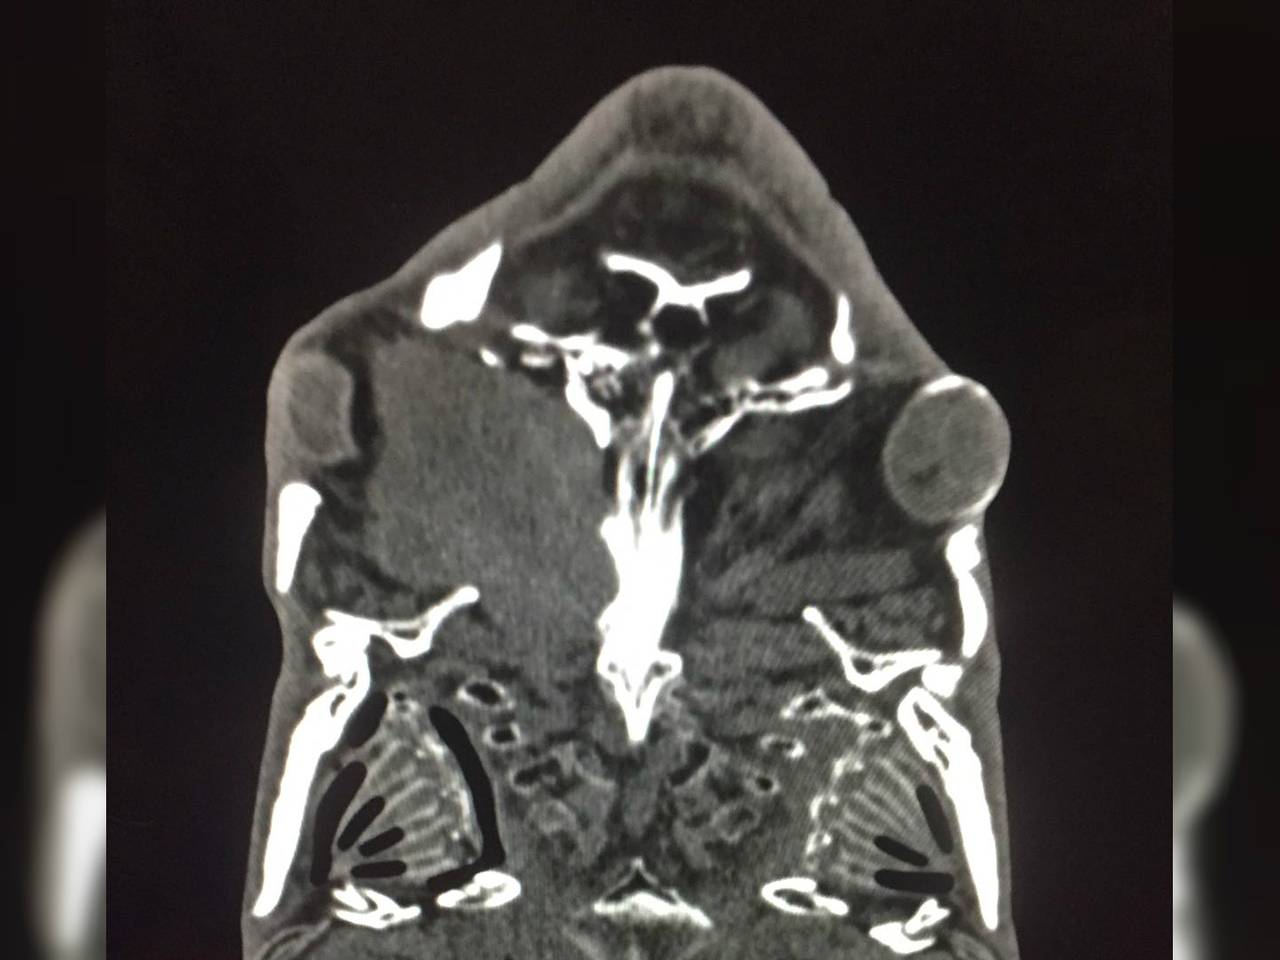

De karper zwom al een tijdje rond met een dik oog. Zijn baasje maakte zich zorgen en nam contact op met dierenarts Rob. Hij heeft zelf geen CT-scan in zijn praktijk, maar wist een kliniek waar er wel een is. De diagnose was niet best: Rob zag een massa die de schedel en de mondholte van het geschubte dier binnendringt.